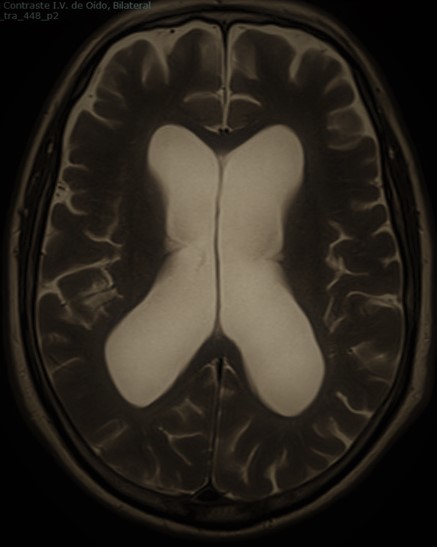

La producción de líquido cefalorraquídeo (en adelante LCR) se sitúa en torno a los 500 ml por día en el adulto. La hidrocefalia tiene lugar cuando existe una acumulación anormal de LCR a nivel intracraneal que provoca una disfunción neurológica.

Sin embargo, la clasificación «clásica» de la hidrocefalia considera como hidrocefalia propiamente obstructiva o no comunicante aquella en la que tiene lugar la «macroobstrucción» (esto es, dentro de las cavidades ventriculares) de la circulación del líquido cefalorraquídeo, generalmente por lesiones que deforman el acueducto de Silvio o el IV ventrículo. Por otro lado se diferenciaría una hidrocefalia comunicante, considerando como tal aquella en la que no existe un impedimento en la circulación de LCR dentro de las cavidades ventrículares pero sí que existe una obstrucción microscópica a nivel de las vellosidades aracnoideas que imposibilita la adecuada reabsorción del LCR.

Dentro de los tipos de hidrocefalia que con mayor frecuencia tratamos se encuentra la «hidrocefalia crónica del adulto». De aparición en adultos en torno a 60-70 años se trata de un tipo de hidrocefalia comunicante caracterizada por la tríada de Hakim-Adams en la que aparece la apraxia de la marcha, la incontinencia urinaria y la demencia. Representa una de las pocas causas de demencia tratables en la actualidad mediante la implantación de una derivación ventriculoperitoneal.